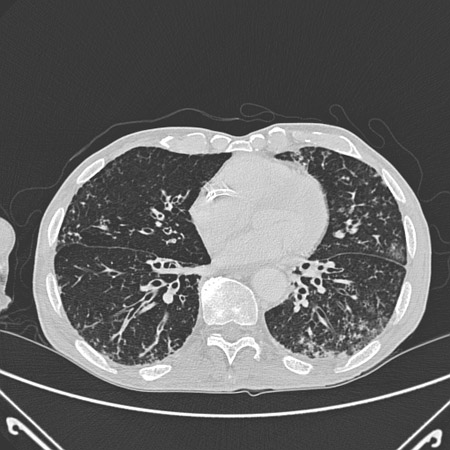

Chest CT with dilated and thickened airways and peripheral tree-in-bud pattern

From archives of Dr Sangeeta M. Bhorade; used with permission